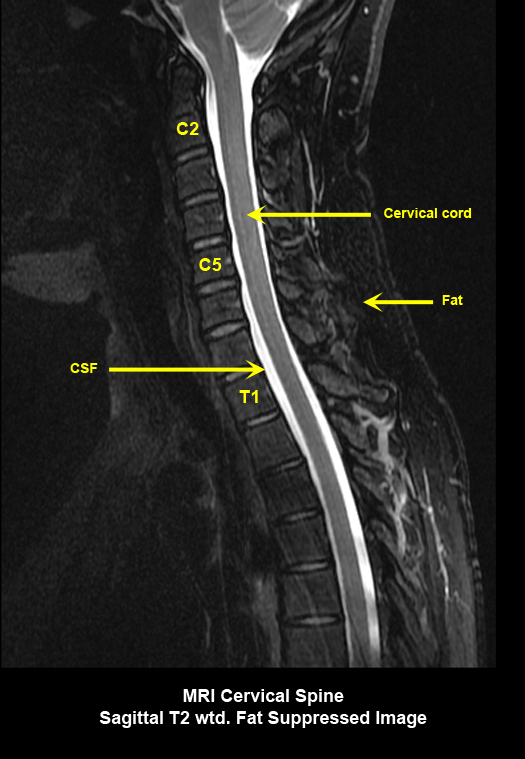

MR Brain and Spine